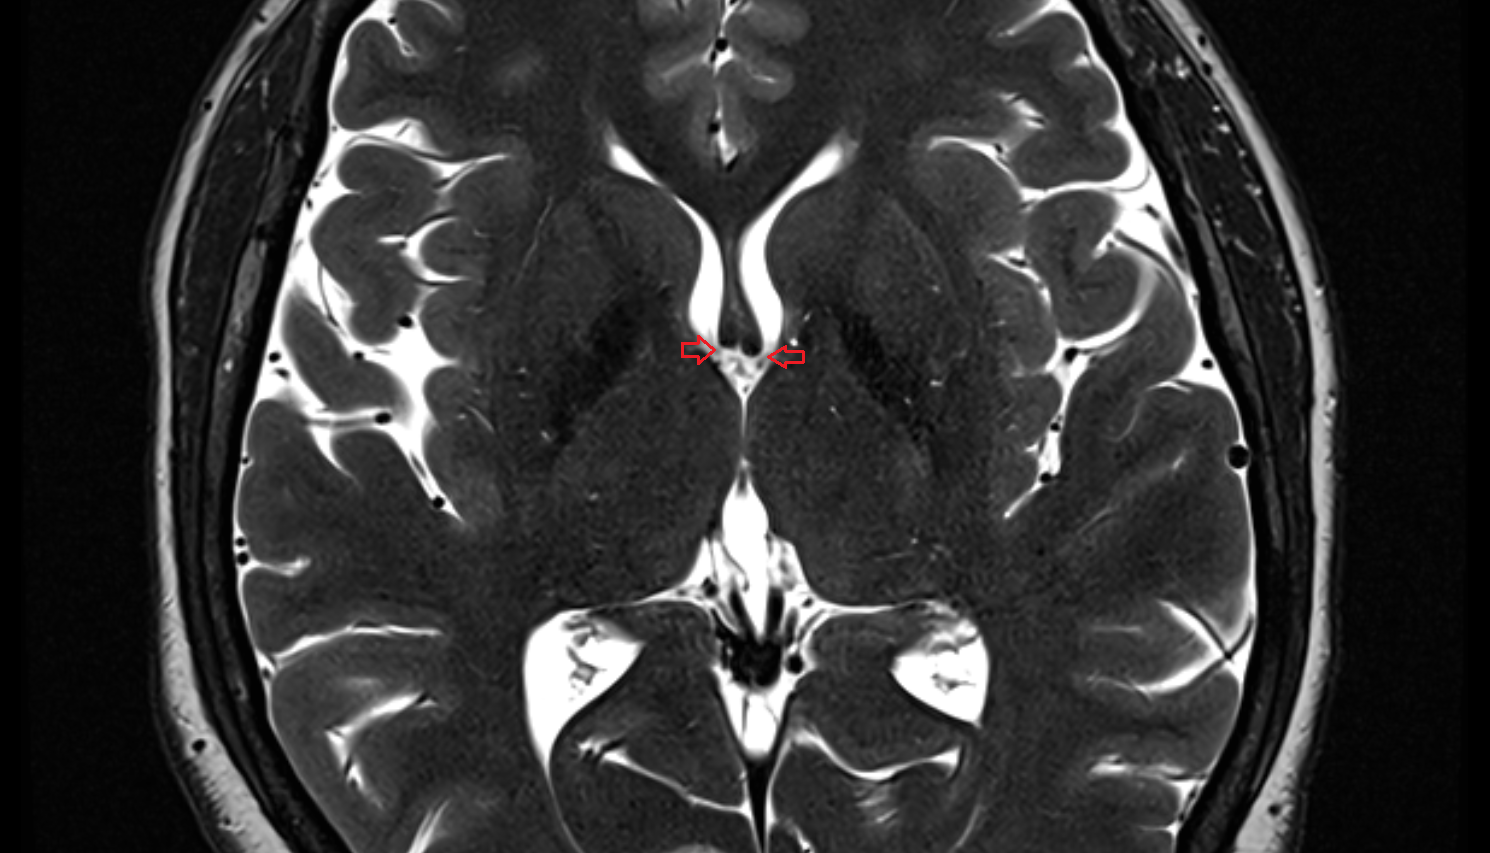

- Cerebral aqueduct